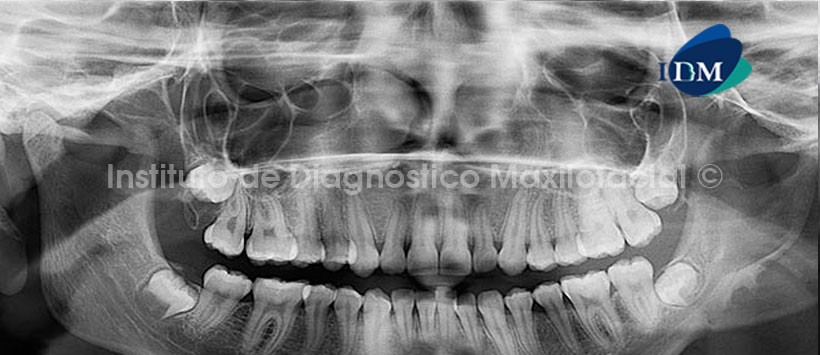

A la evaluación Panorámica (Fig.1) se observa la severa alteración morfológica que compromete cuerpo, ángulo y rama ascendente del lado izquierdo, así como el marcado aplanamiento del contorno condilar. Se observa también contornos irregulares dependientes de la basal mandibular a nivel de la zona afectada, por otro lado se evidencia perdida de la densidad ósea nivel de la rama mandibular, distinguiendo que los límites de la mencionada alteración convergen en el conducto dentario inferior, sugiriendo una imagen radiográfica semejante a la de un embudo. Además se observan el leve aumento de las dimensiones del agujero mentoniano. Por otra parte, se aprecia también la probable presencia de un doble canal mandibular en el lado derecho.